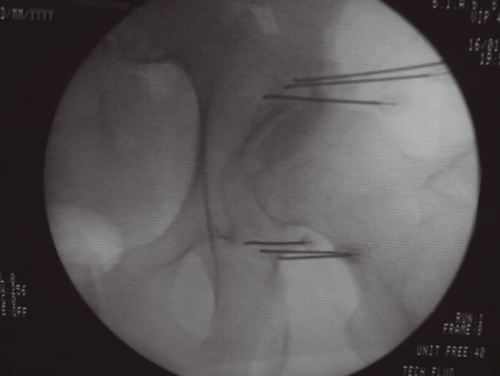

Figura 2